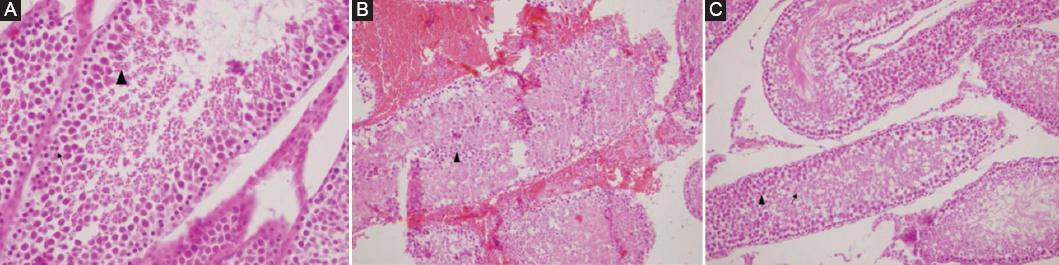

A statistically significant difference was found between group 1-group 2 and group 2-group 3 when comparing the JTBS values of the groups in pairs. There was no significant difference between Group 1 and group 3 (p < 0.05). Values are given in table 2. Histopathological images in all three groups are shown in figure 2.

Figure 2 A: sertoli cell, spermatogonia (↑), and Spermatocyte (▲) in testicle of group 1. B: diffuse fresh bleeding in the interstitial area and exfoliated necrotic cells in seminiferous tubule lumen, few ghost germinal epithelial cells in the left testicular tubule lumen belonging to group 2 (▲) (H&E ×100). C: Spermatids (↑) and spermatozoons (▲) in the testis belonging to group 3.